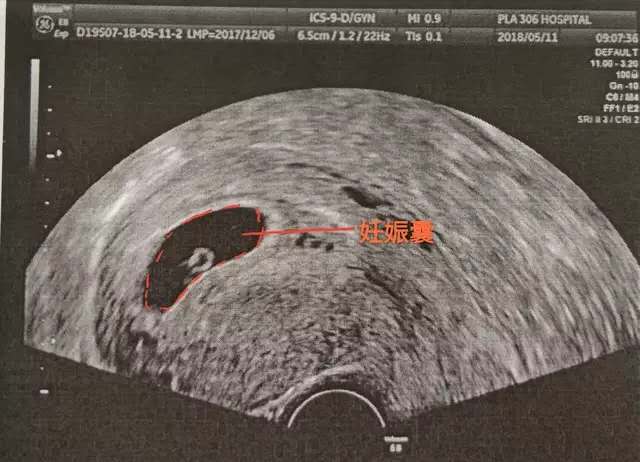

第一部曲孕囊 对于孕囊大家应该不陌生,停经42天(6周)时,宫腔内可见到圆形或椭圆形的妊娠囊(孕囊),孕囊是原始的胎盘组织,被羊膜,血管网包裹的小胚胎,是怀孕最初的形态。提示宫内孕,此时孕囊一般占宫腔的1/4。